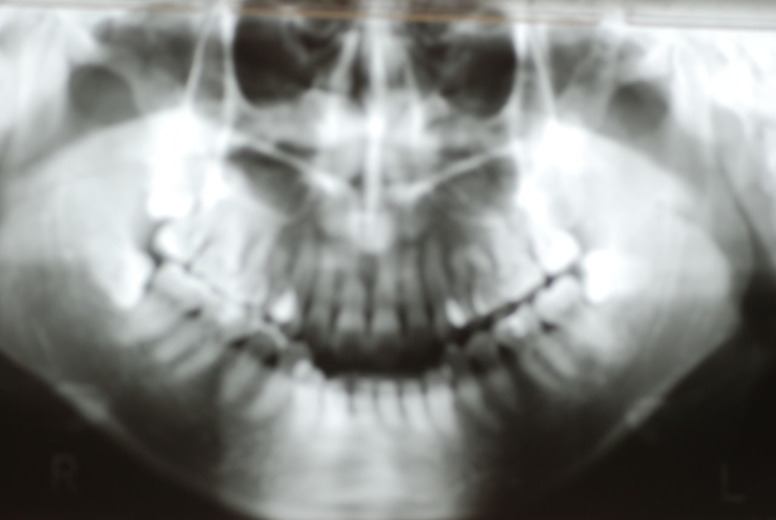

隣の14歳大臼歯がひどい虫歯になり治療不可能になりつつある状態のレントゲン